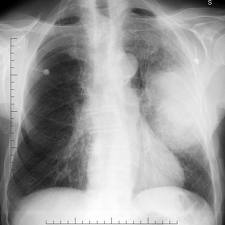

Bronchogenic-carcinoma-x-ray.jpg Investigations

X- ray

shows :

- Coin shadow - Cavity, collapse.

- Mediastinum mass - Diaphragmatic paralysis

- Effusion - Rib erosion